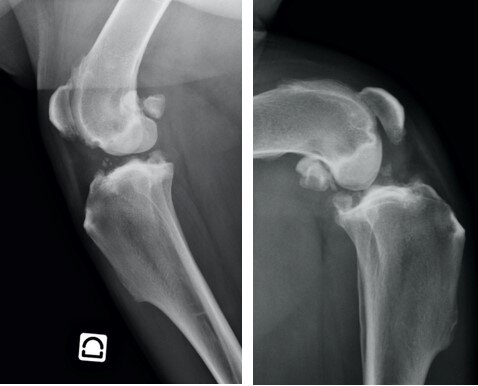

Mastiff femelle, 7 ans, 67 kg

Arthrose bilatérale sévère des grassets avec ankylose. Score Dolodog 31 : Douleurs sévères sans composante neuropathique associée. Intolérance digestive aux AINS. La prise quotidienne de tramadol (200 mg le matin, 100 mg le soir) depuis 1 an permet au chien de se relever et de diminuer le ressenti douloureux sans améliorer significativement la fonction. Le nomadisme médical du propriétaire est dû à des avis très contradictoires sur l’opportunité d’une double TPLO. L’injection intra-articulaire de cellules souches mésenchymateuses néonatales a permis une récupération fonctionnelle spectaculaire et durable (26 mois à ce jour) : score Dolodog 10-14 ; la prescription de tramadol est renouvelée pour gérer les accès paroxystiques (environ 40 administrations au cours des 780 jours de suivi).